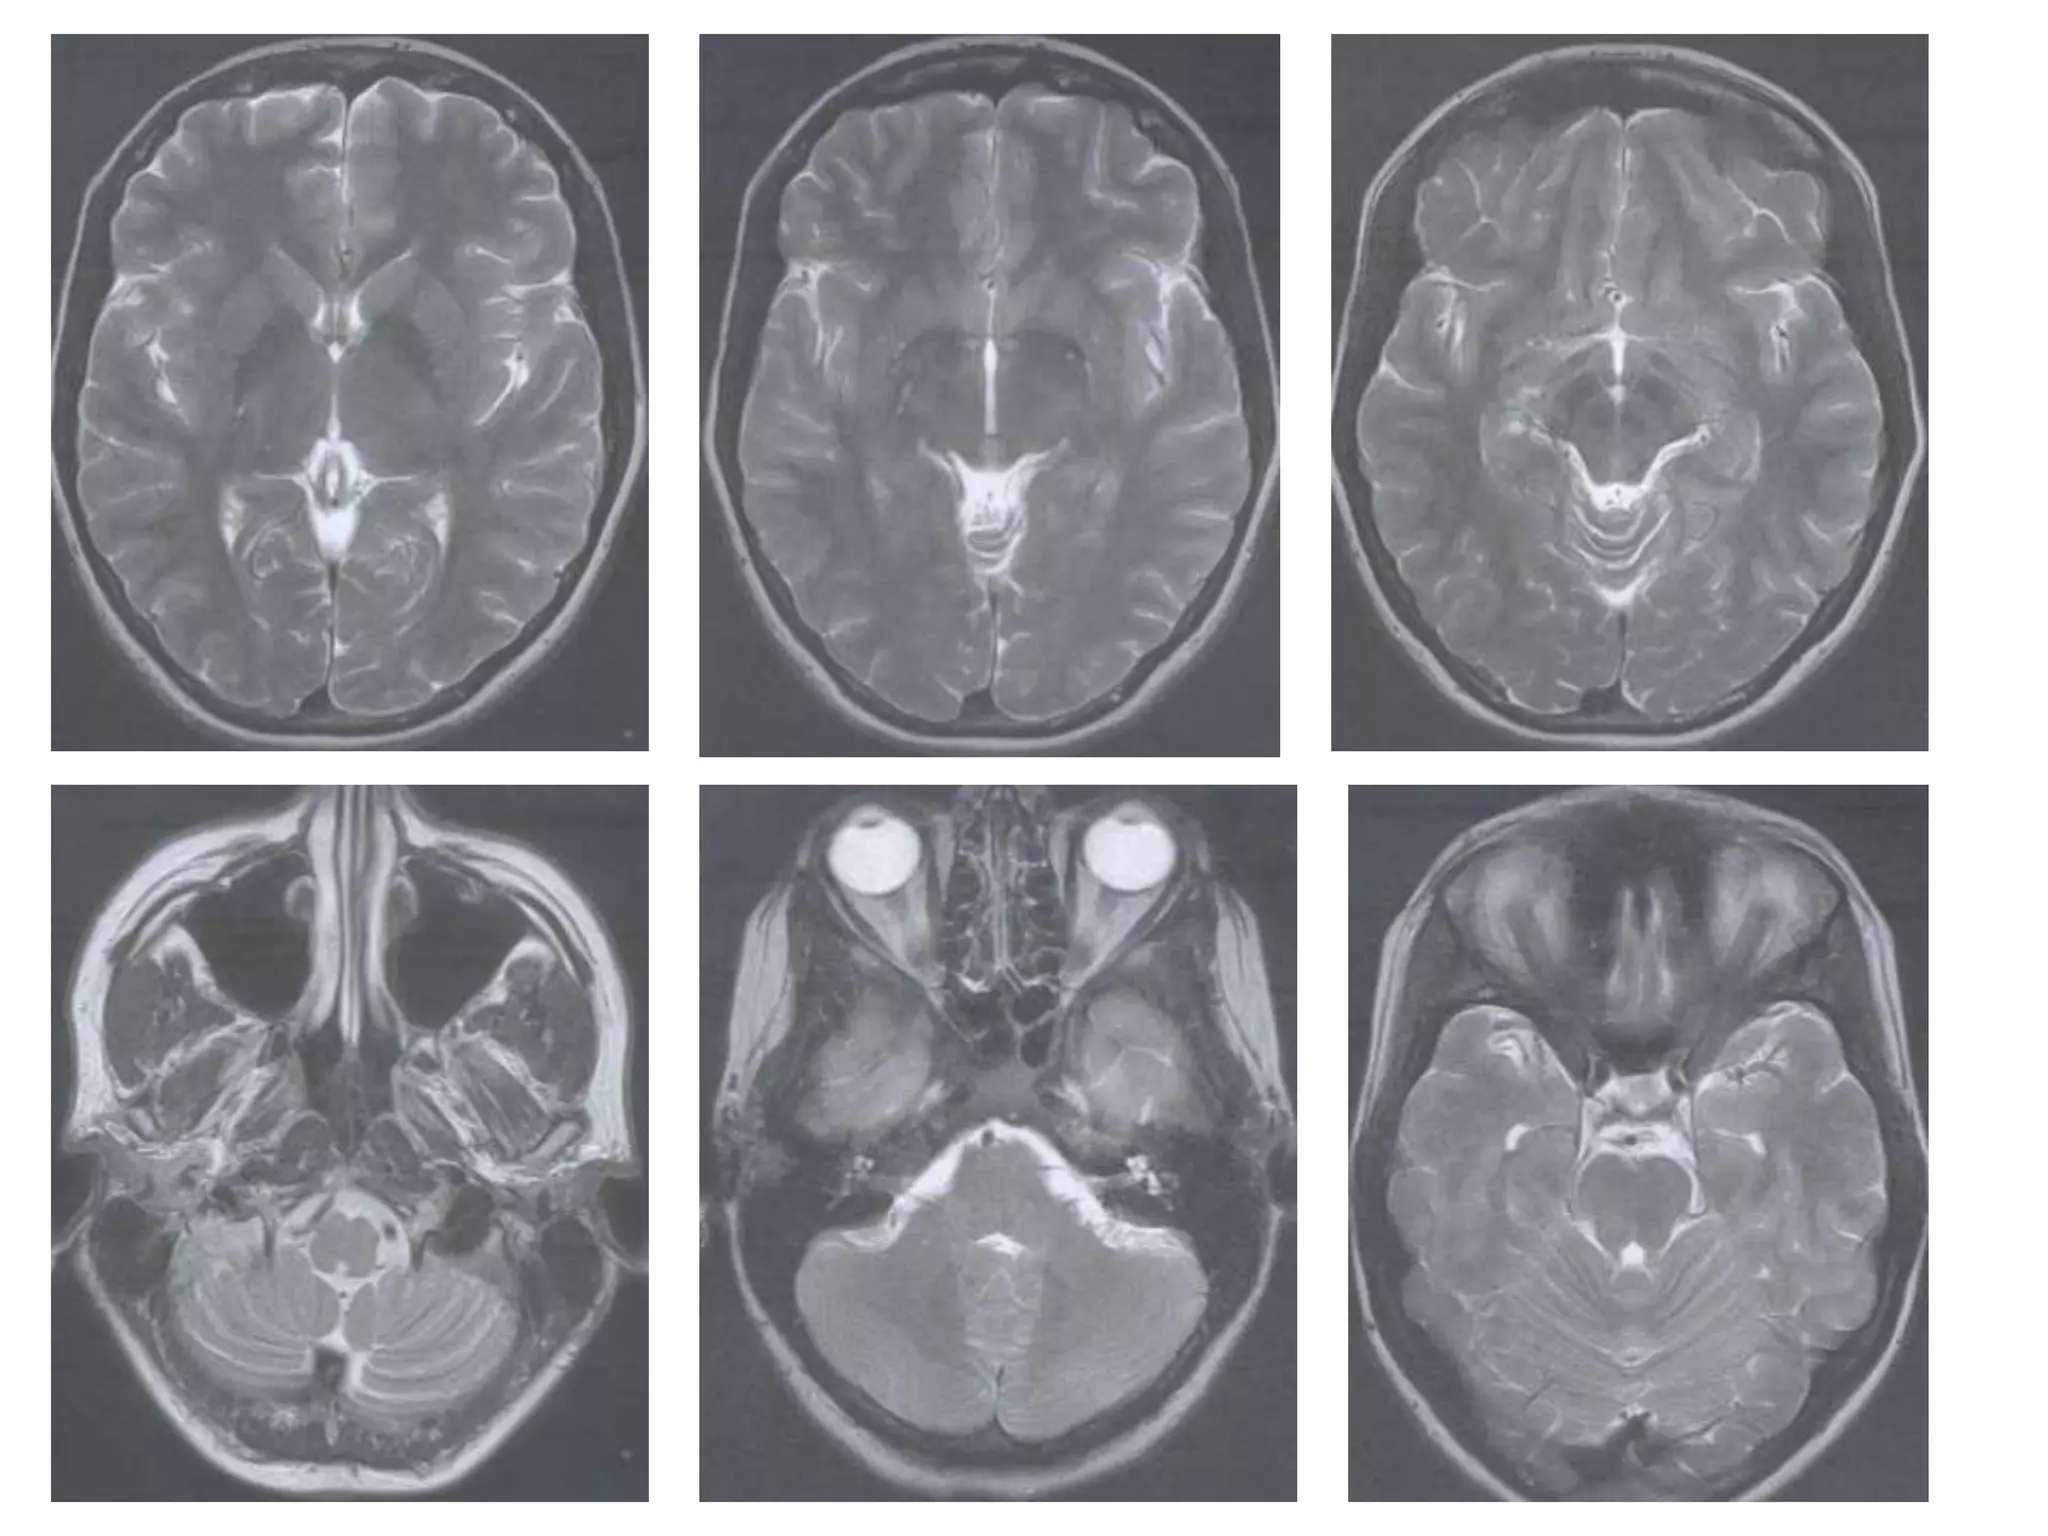

Radiology

• Axial MRI / CT – ‘kidney bean’ turned on its side.

• Saggital MRI - mid point of line drawn b/w T. sella

and trocula should intersect middle of 4th

ventricle.

• Coronal MRI – elongated rhomboid shape

• Radiology –

Axial MRI / CT : frontal horns separated by

S. pellucidum and posteriorly lateral ventricles diverge

and pass into temporal and occipital horns.